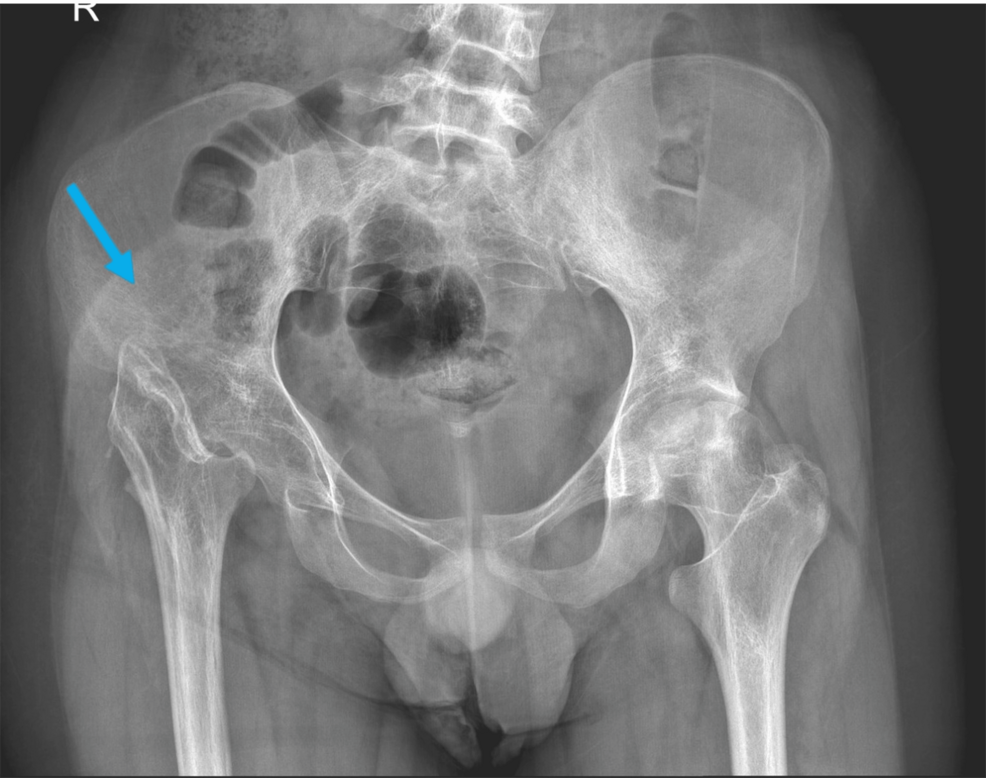

Preoperative radiographs after seven decades of Girdlestone situation Girdlestone X Ray Radiopaque material in the left femoral intramedullary. The girdlestone resection arthroplasty (gra) is a salvage procedure for a recurrent or persistent. the girdlestone procedure (also known as a femoral head ostectomy or girdlestone resection arthroplasty) is an. girdlestone is one of the options for treating an infected hip arthroplasty (along with isolated. girdlestone arthroplasty and hip arthrodesis. Girdlestone X Ray.

Preoperative radiographs after seven decades of Girdlestone situation Girdlestone X Ray girdlestone arthroplasty and hip arthrodesis using the ilizarov external fixator as a salvage method in the management. girdlestone is one of the options for treating an infected hip arthroplasty (along with isolated. The girdlestone resection arthroplasty (gra) is a salvage procedure for a recurrent or persistent. the girdlestone procedure (also known as a femoral head ostectomy or. Girdlestone X Ray.

Preoperative radiographs after seven decades of Girdlestone situation Girdlestone X Ray girdlestone arthroplasty and hip arthrodesis using the ilizarov external fixator as a salvage method in the management. Radiopaque material in the left femoral intramedullary. the girdlestone procedure (also known as a femoral head ostectomy or girdlestone resection arthroplasty) is an. girdlestone is one of the options for treating an infected hip arthroplasty (along with isolated. The girdlestone. Girdlestone X Ray.